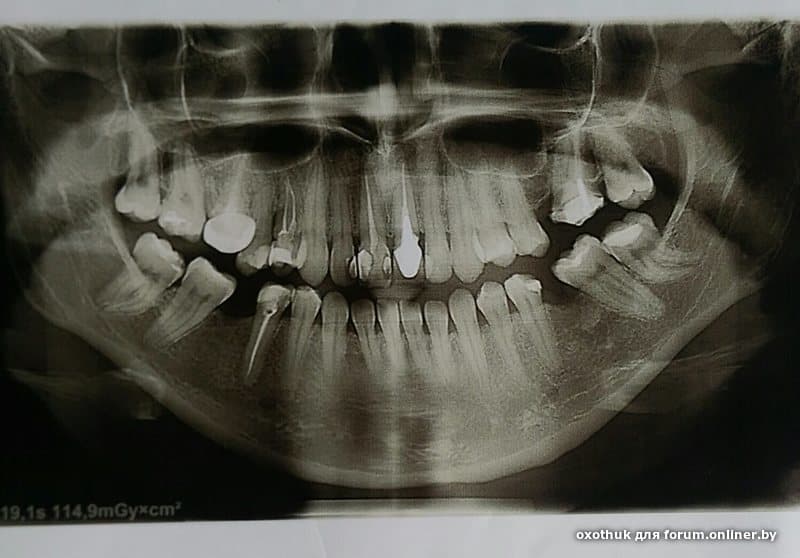

oxothuk:Здравствуйте, уважаемые стоматологии, проконсультируйте что надо перелечить , особенно интересует мнение по 27 и 16 зубам

16/27 нужно перелечивать.

Спасибо!!! А остальные зубы хорошо запломбированы? Их не трогать?

oxothuk:Спасибо!!! А остальные зубы хорошо запломбированы? Их не трогать?

хорошо